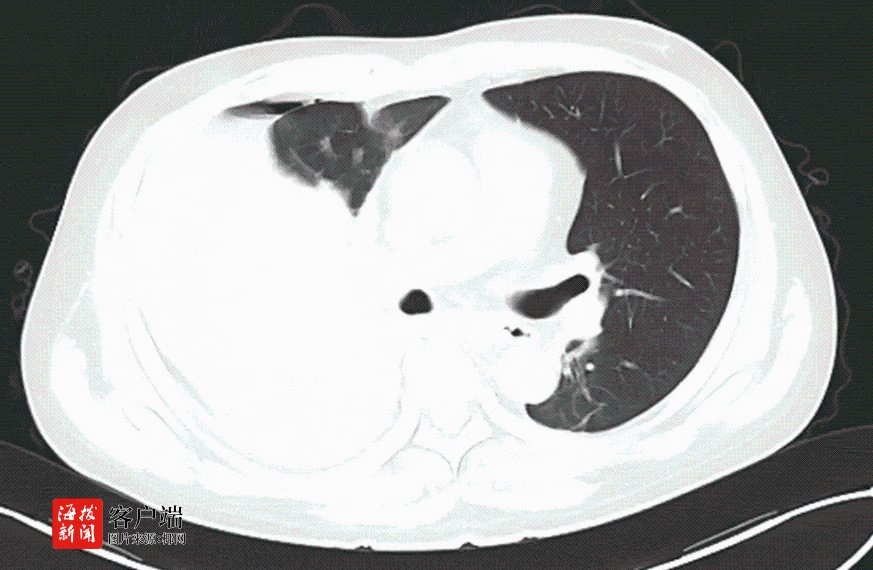

据了解,卢先生因车祸被120紧急送入该院救治。入院时,医护人员迅速检查发现,他不仅右侧液气胸(少量)、创伤性湿肺、椎体压缩性骨折,还出现了面色苍白、心率加快、血压下降,血色素急剧下降等症状。胸部CT检查更是显示,他的右侧胸腔大量积血,肺压缩高达80%,右胸腔大片高密度影较前增大,生命岌岌可危。

面对如此危急的病情,医护人员在急诊床旁为卢先生行右侧胸腔闭式引流术,胸腔引流管引出大量暗红色血性液体。该院胸外科副主任刘运仲也迅速赶到现场会诊。他凭借丰富的急救经验,果断判断卢先生胸外伤未合并肋骨骨折,但有大量气胸,肺部破裂,右胸腔大片高密度影及胸腔引流出的大量血性液体均提示有胸腔大出血的情况,但大出血原因不明。考虑到卢先生发病突然,且疾病进展快,凶险程度高,时间紧迫,他立即向胸外科主任赵宏光汇报,并准备进行手术探查止血。